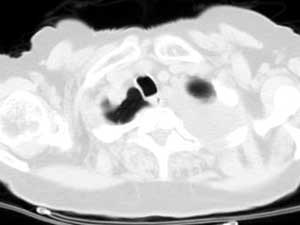

标题: 回复:病历讨论,胸膜间皮瘤?(是同一个病人吧)

从图片看,包裹性积液好象更合理,梭形,ct值3-5hu(在哪看到的?);胸膜间皮瘤如此规则,不多见。

左侧背部胸膜肥厚,伴包裹性积液,不考虑间皮瘤.

同意以上各位的高见,首先考虑包裹性积液,1.胸膜间皮瘤积液量一般较大,以游离性积液更为常见,2.可以看到增厚的胸膜结节